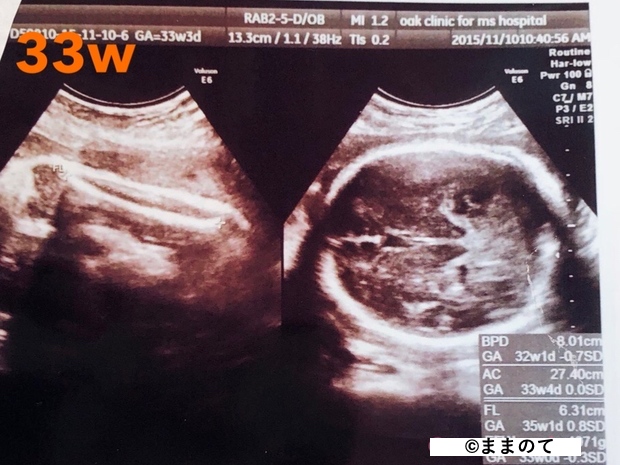

妊娠9ヶ月(32・33・34・35週)

このころの身長は約45cm、体重は2,000~2,400gになります。エコーでは全体像をとらえることが難しく、エコー写真には赤ちゃんの身体がアップで写し出されます。鼻や目などのパーツがくっきりと見えることもありますよ。

大腿骨や腹部の断面図だと、後で見たときにどこを写したのかわかりづらいため、写真を受け取る際に医師に確認しておくと良いでしょう。